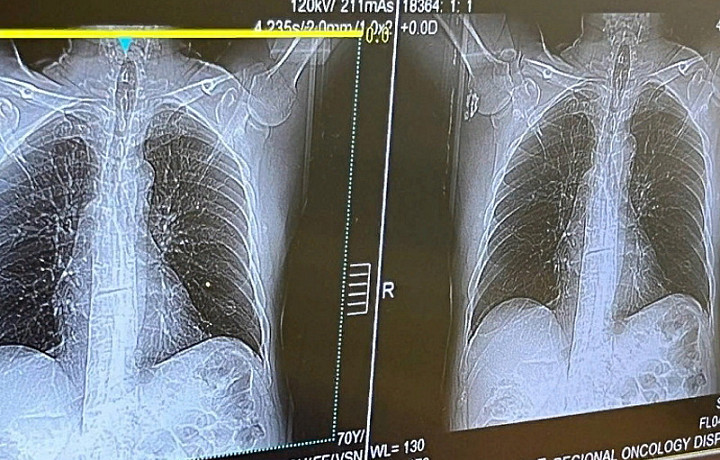

240 туляков прошли диагностику на наличие злокачественных новообразований в рамках Дня открытых дверей 26 ноября в поликлинике Тульского областного клинического онкологического диспансера.

Жители Тульской области прошли раннюю диагностику онкологических заболеваний, курильщики со стажем сделали низкодозную компьютерную томографию легких.

Женщины прошли обследование молочных желёз с помощью УЗИ и маммографии, а также посетили гинеколога. Мужчины сдали анализ крови на ПСА. Так, в рамках исследования были обнаружены одно онкозаболевание и 11 подозрений на онкопатологию.